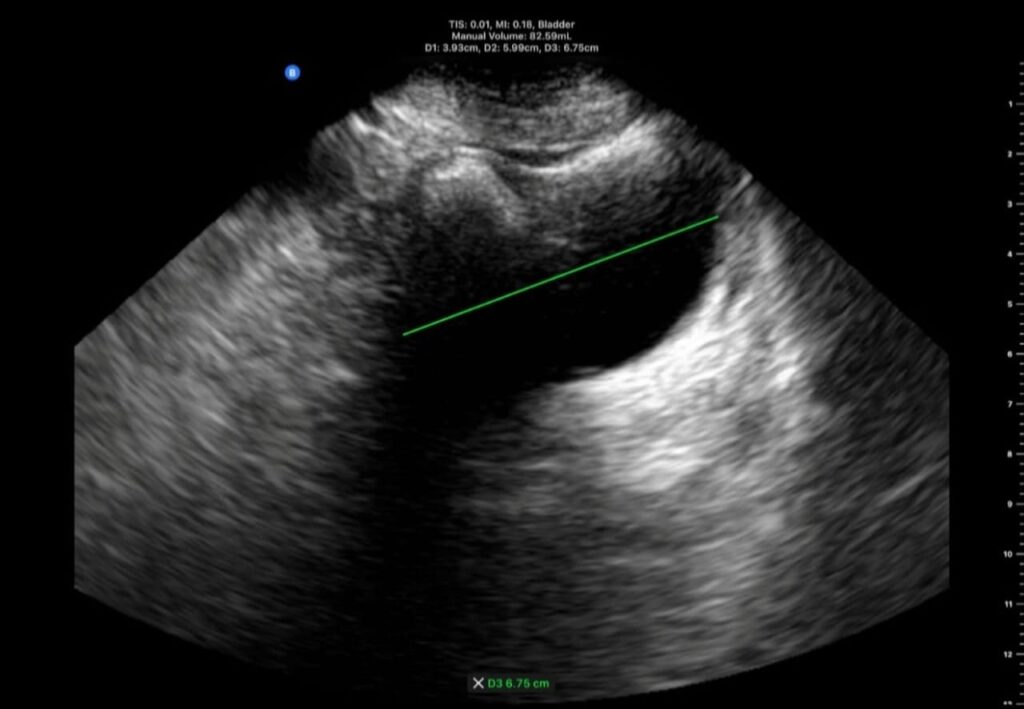

A 78-year-old male. Degenerative Parkinsonism. Bladder US, post-void volume = 87 ml